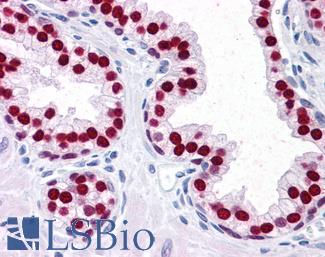

Anti-CDX2 antibody IHC of human colon. Immunohistochemistry of formalin-fixed, paraffin-embedded tissue after heat-induced antigen retrieval. Antibody LS-B1514 concentration 5 ug/ml. This image was taken for the unconjugated form of this product. Other forms have not been tested.

CDX2